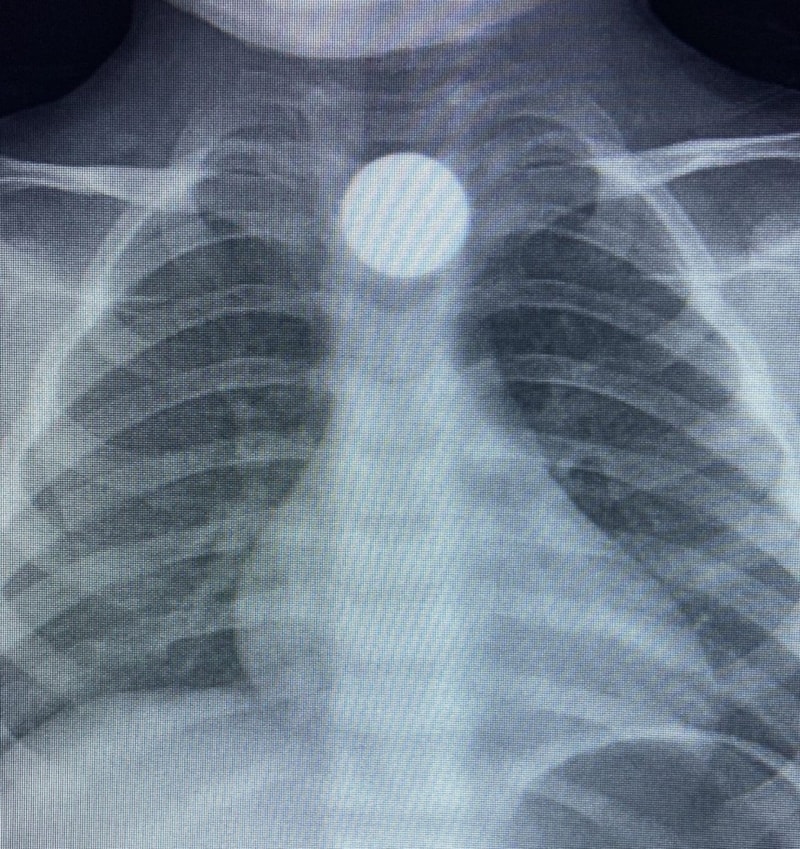

Çocuğun parayı yuttuğunu fark eden ailesi, Bilal K.’yi vakit kaybetmeden özel araçla İnegöl Devlet Hastanesi’ne götürdü. Hastanede yapılan muayene ve görüntüleme işlemlerinde, madeni paranın çocuğun yemek borusunda takılı kaldığı tespit edildi.

İlk müdahalesi İnegöl Devlet Hastanesi’nde yapılan Bilal K., ileri tetkik ve tedavi amacıyla ambulansla Bursa Yüksek İhtisas Eğitim ve Araştırma Hastanesi’ne sevk edildi.